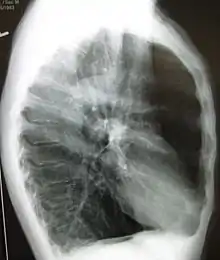

مقطع بالصدر بالتصوير الطبقي المحوري

حالة متقدمة من انتفاخ الرئة